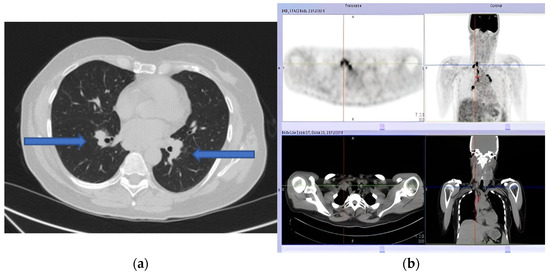

Our patient presented to the Emergency Department with House–Brackmann scale grade V (corresponding to severe dysfunction, barely perceptible motion, and asymmetry at rest) right peripheral FNP. Her past medical history included situational depression with anxiety and mild tension-type headache occurring since adolescence. She was on no medications, and she denied any tobacco, alcohol, or drug abuse, exposition to toxic agents, or recent infection. Vital parameters were normal. Lungs auscultation and abdomen evaluation were unremarkable. Herpes Zoster infection was first excluded by searching for vesicles or scabbing. Then, a complete neurological examination showed right tongue deviation, impaired sensation to the right side of the face, and an alteration to taste sensation. A brain CT scan ruled out a cerebrovascular accident of posterior circulation. Subsequent brain MRI with contrast was normal. A complete blood count and a comprehensive metabolic panel showed no abnormality. A routine chest X-ray showed multiple bilateral lymphadenopathies confirmed by chest CT (Figure 1a). We excluded occult neoplasia, performed a mammography and breast ultrasound (BI-RADS 1 bilaterally), and planned a total body PET scan (Figure 1b).

Figure 1. (a) Pulmonary computed tomography (CT) scan showing multiple bilateral lymphadenopathies. (b) Positron emission tomography (PET) showing multiple adenopathies with a high metabolic component.

After a week, she presented with left peripheral FNP, bilateral hearing loss, limitation in left gaze, expression of left sixth cranial nerve palsy, and liquid dysphagia. The examination confirmed the presence of cranial multineuritis. Following readmission, a lumbar puncture was performed with cerebrospinal fluid (CSF) analysis showing a slight increase in cell count (17 cells/mm3—monocytes), normal protein (31 mg/dL), and glucose level (70 mg/dL); malignant cells were not seen on cytology. The PET scan showed multiple supraclavicular, paratracheal, epiaortic, paraesophageal, and parahilar adenopathies with a high metabolic component. Serological tests, including ANCA, ANA, HIV antibody test, tuberculosis, and B.Borrelia serology, were negative, but the sedimentation rate of the erythrocytes (ESR) was 24 mm/h. Flow cytometry was not performed. Based on clinical presentation and exam results, the suspect of a granulomatous disorder was made, and corticosteroid therapy (1 mg/kg of prednisone–55 mg/day) was started with a partial clinical benefit over four days. A needle biopsy was performed via bronchoscopy and showed epithelioid macrophages in granulomatous aggregation to characterize the lymph node alterations (Figure 2).